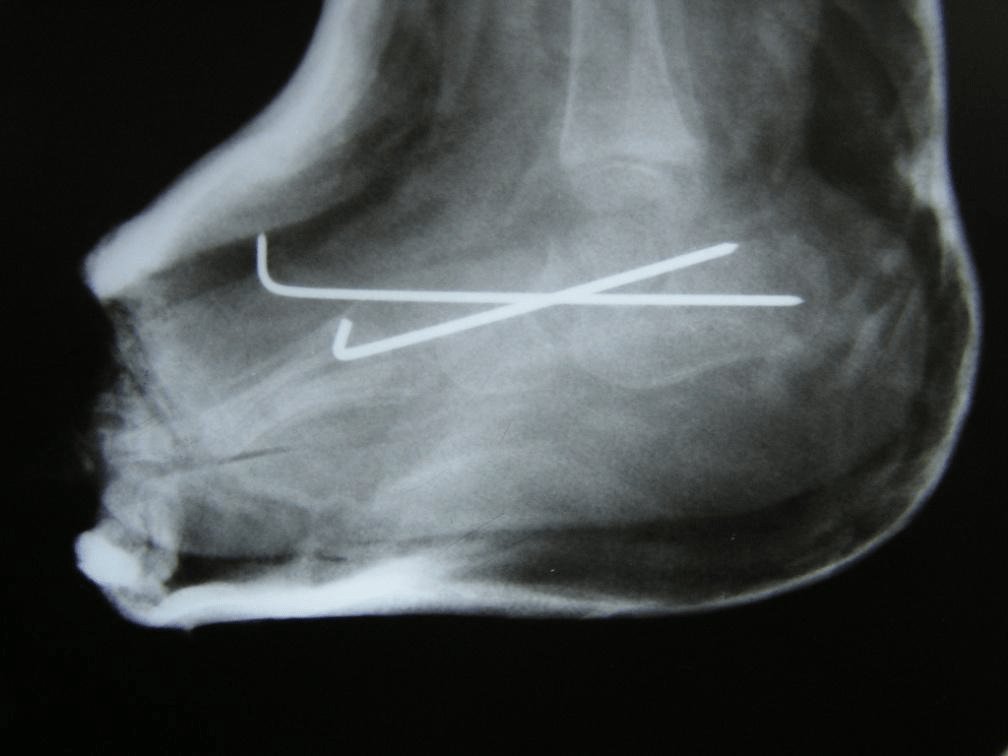

Figure 4: Post-op lateral views of both feet. The talo-navicular joints have been reduced and fixed.